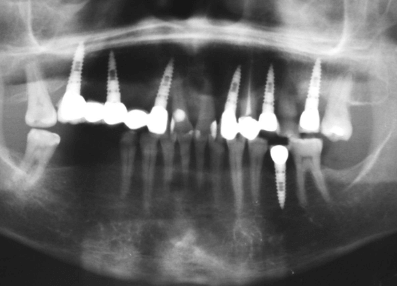

치아 건강은 관리도 중요하지만, 역시나 유전자의 힘은 어찌할 수가 없습니다. 너무나도 건강한 우리집 아버지도 이빨만큼은 지키지 못해 한 번에 10여개의 치아를 임플란트 해야 했는데, 상당히 힘든 과정을 거쳤습니다. 저 역시도 핏줄을 속일 수 없기에 현재까지는 하나만 했지만, 머지않아 여러 개를 해야할 것 같네요. ㅠㅠ

4) 잇몸뼈 상태와 건강 상태 : 잇몸뼈가 부족하면 뼈 이식이 필요하며, 당뇨병·골다공증 환자는 치료가 제한될 수 있습니다. 수술 전 기본 건강 상태를 체크해야 하며, 흡연자는 회복 속도가 느릴 수 있습니다.